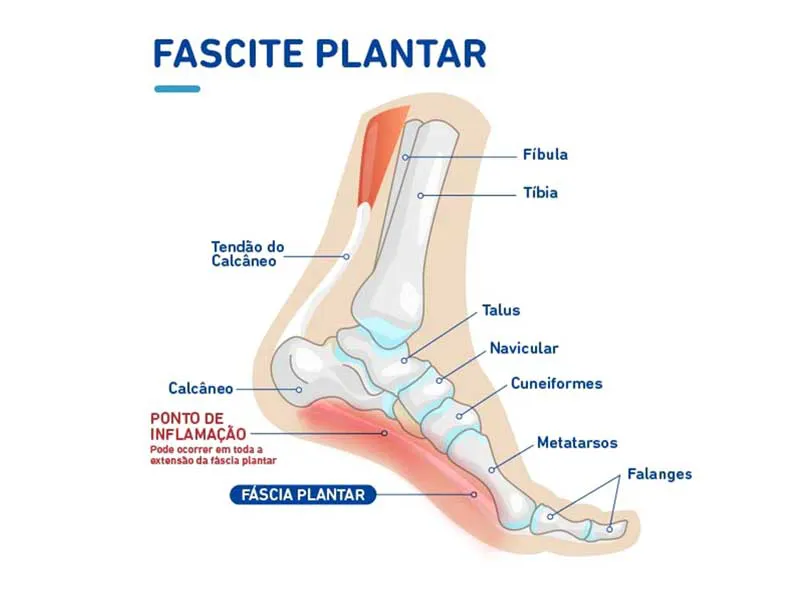

A fascite plantar é uma condição dolorosa que se localiza na região inferior do calcanhar, é uma patologia que ocorre como consequência de micro lesões repetitivas e inflamação crônica na fáscia plantar, principalmente na região de inserção no tubérculo medial do osso calcâneo.

A fáscia plantar é uma faixa grossa de tecido que fica na sola do pé. Ela começa no osso do calcanhar e vai até a base dos dedos, funcionando como uma espécie de “cinta elástica” que ajuda a sustentar o arco do pé. Sua função é dar estabilidade ao pé e absorver o impacto quando caminhamos, corremos ou ficamos em pé.

A fascite plantar se desenvolve quando a fáscia plantar é submetida à sobrecarga e, em consequência, sofre micro lesões que superam a capacidade do corpo de se curar.